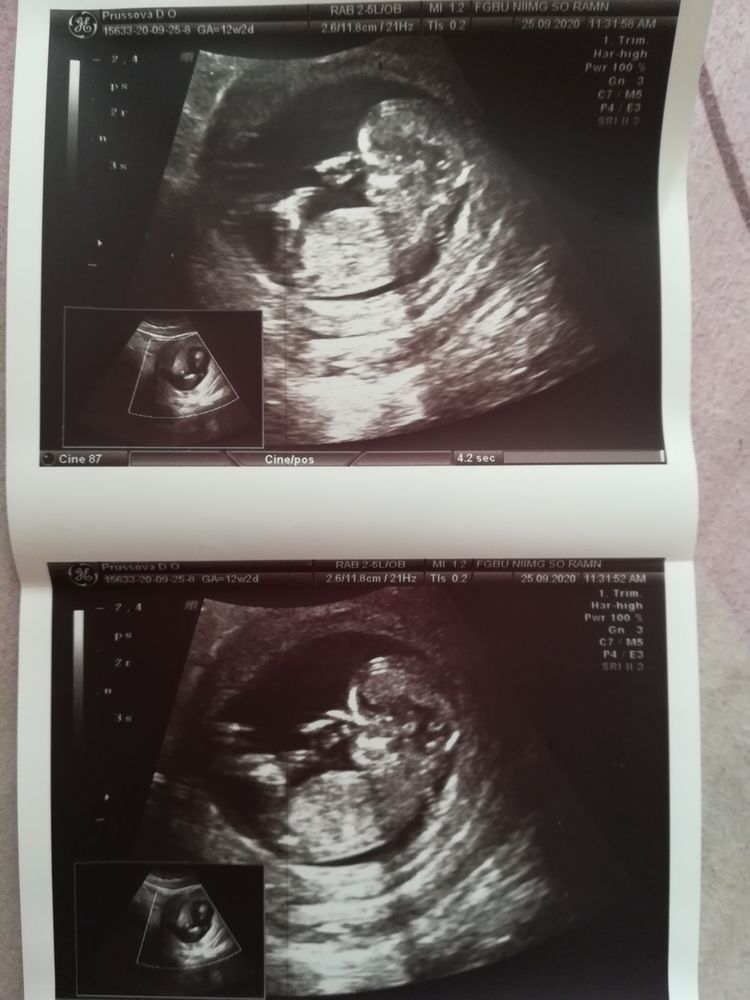

Первый скрининг

УЗИ, КТГ, доплерНаконец то я его прошла, вытерпела целый месяц без узи со своей паникой)) Всё в норме, результаты не дали, вроде надо потом забирать, а хотелось посмотреть параметры своей крохи.

Купила фотографии, видео записать не получилось 😒 Малыш вёл себя очень спокойно, а я ждала, что будет сальтухи наворачивать как у всех))

Кто разбирается в поле, можете разглядеть что нибудь? 😄